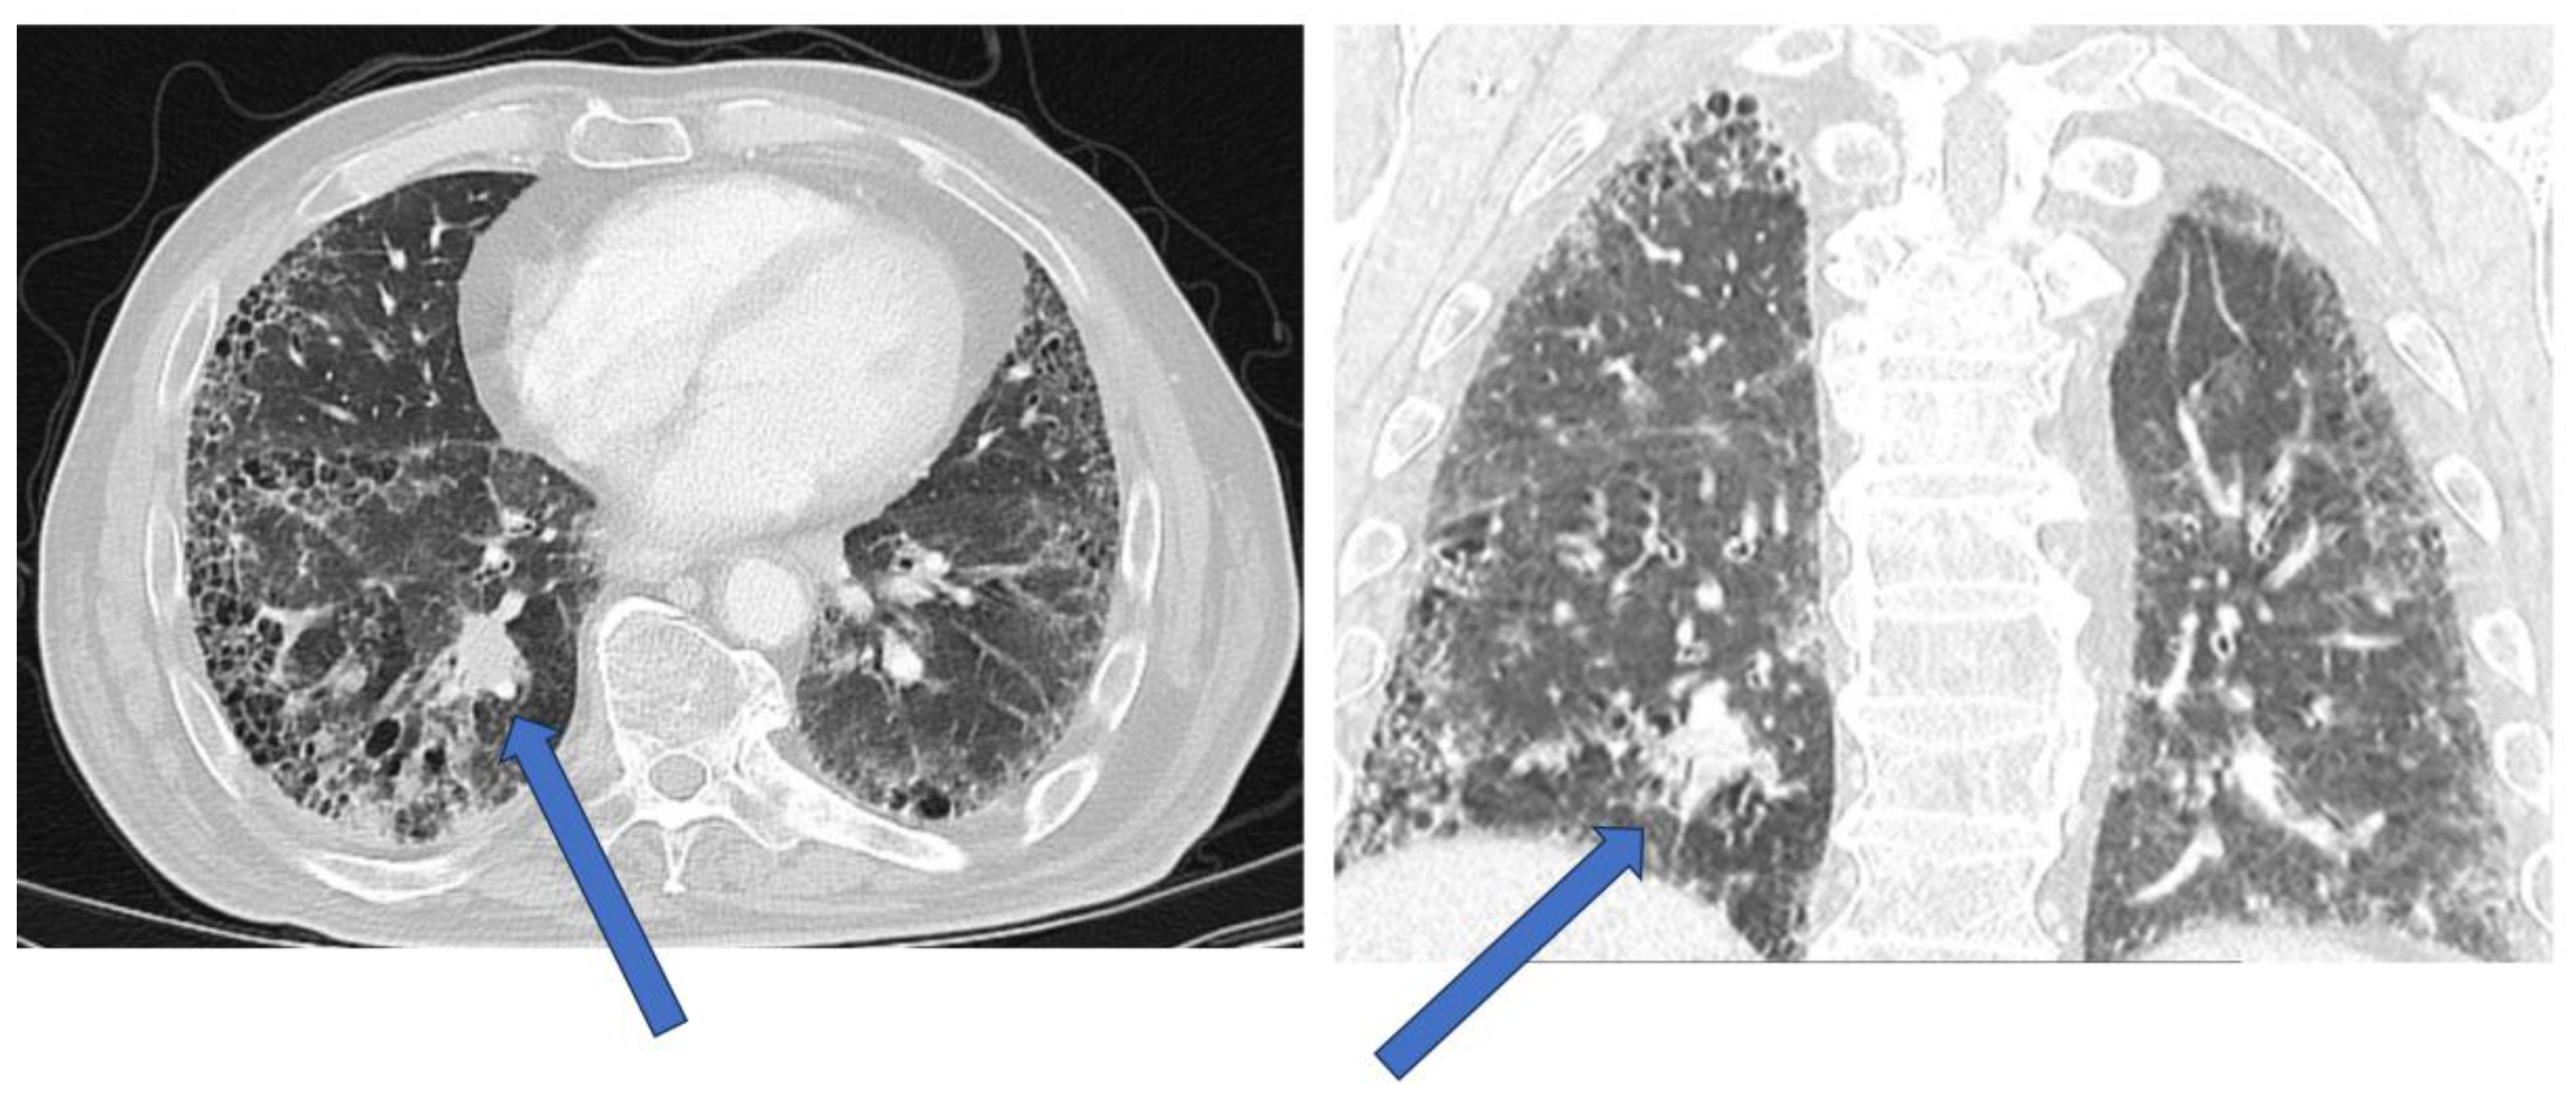

| HRCT | Tumors may be directly adjacent to fibrotic lesions, with underestimation of tumor size. Reduced sensitivity and specificity in evaluating mediastinal lymph nodes (reactive mediastinal lymph node enlargement may be seen in ILDs without lung cancer) |